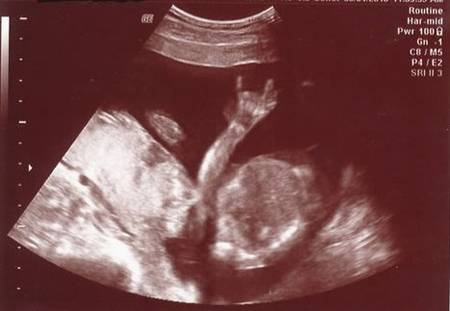

Nu mereu reușești să surprinzi atât de bine anumite imagini de ecograf. Tocmai de aceea, imaginile prezentate sunt foarte RARE!

De-a lungul timpului au fost surprinse mai multe imagini de ecograf cu adevărat uluitoare!

Iată mai jos 10 imagini de ecograf unice!